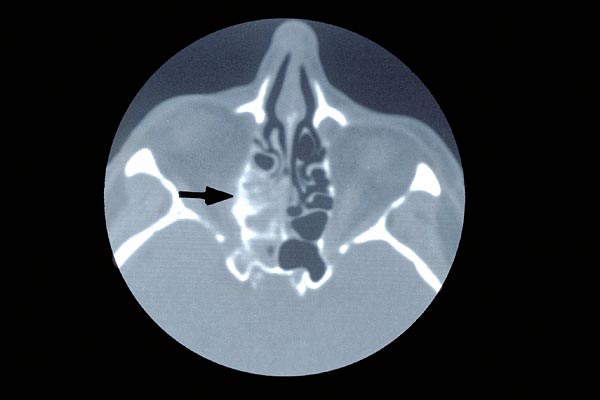

Als weitere Ursache für eine Verlegung der Nasenatmung ist an alle Tumoren zu denken, die meist von der Nasenschleimhaut ausgehen. Hier nimmt die Behinderung sukzessive zu. Sie ist fast immer einseitig.

Tumoren der Nasenschleimhaut